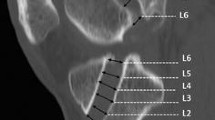

All surgeries were performed using standardized procedures for anatomic ACLR. The procedures for anatomic DB ACLR and SB ACLR have been published [22]. To avoid graft type as a confounding factor, a 10 mm-wide autograft quadriceps tendon with a patellar bone block was used in all cases [12]. For DB ACL reconstruction, the 10 mm-wide quadriceps tendon graft was split, leaving the bone block as one, into grafts to reconstruct the anteromedial (AM) bundle and the posterolateral (PL) bundle. To minimize bias with graft harvest, the harvest was completed before the subject was randomized into the SB or DB group. For DB ACLR, one femoral tunnel in the center of the femoral insertion site and two tibial tunnels corresponding to the insertions of the AM and PL bundles were created to reproduce the normal insertion site anatomy. For SB ACLR, one femoral and one tibial tunnel were created in the center of the femoral and tibial insertion sites, respectively (see Fig. 1a, b). If necessary, meniscus repair or meniscectomy or chondroplasty was performed.

a Mean side-to-side differences (SSD; ACLR-contralateral) in tibio-femoral kinematics (anterior tibial translation, flexion, abduction, internal rotation and functional graft length) during the stance phase of downhill running (first 10% of the running cycle) for SB and DB groups at 6 and 24 months after surgery. b, c Statistical pattern matching (SPM) results comparing SSD between SB and DB at 6 (b) and 24 (c) months after surgery. Dashed red line represents the F value threshold corresponding to statistical significance (p < 0.05). No significant differences were found for side-to-side differences between SB and DB